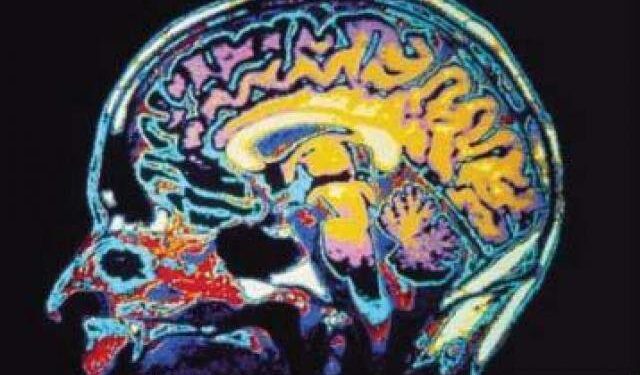

Человеческий мозг также деградирует с возрастом, теряя клетки мозга. Это приводит к таким состояниям, как болезнь Альцгеймера, которая может привести к деменции. Клетки мозга содержат каннабиноидные рецепторы, поэтому теория состоит в том, что поддержание оптимального уровня каннабиноидов в организме может помочь сохранить жизнь клеткам мозга или даже генерировать новые каннабиноидные рецепторы, чтобы «впитать» все лишние каннабиноиды в организме! Вот почему считается, что каннабиноиды, такие как CBD, способствуют нейрогенезу.